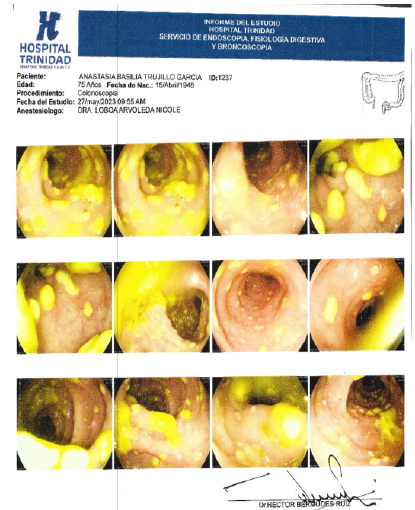

A Dilemma in Diagnosing and Managing Amoebiasis Colitis and Ulcerative Colitis: Case Report

M Cherkaoui Malki, H Elbacha, N Benzzoubeir and I Errabih. 10(6): 47-49.

Intestinal Microbiota Transplantation and Clostridiodes difficile. A Relevant Case

Álvaro Zamudio Tiburcio, Héctor Bermúdez Ruiz, Silverio Alonso López, Pedro Antonio Reyes López and Martín Julián Carrillo. 10(6): 01-06.